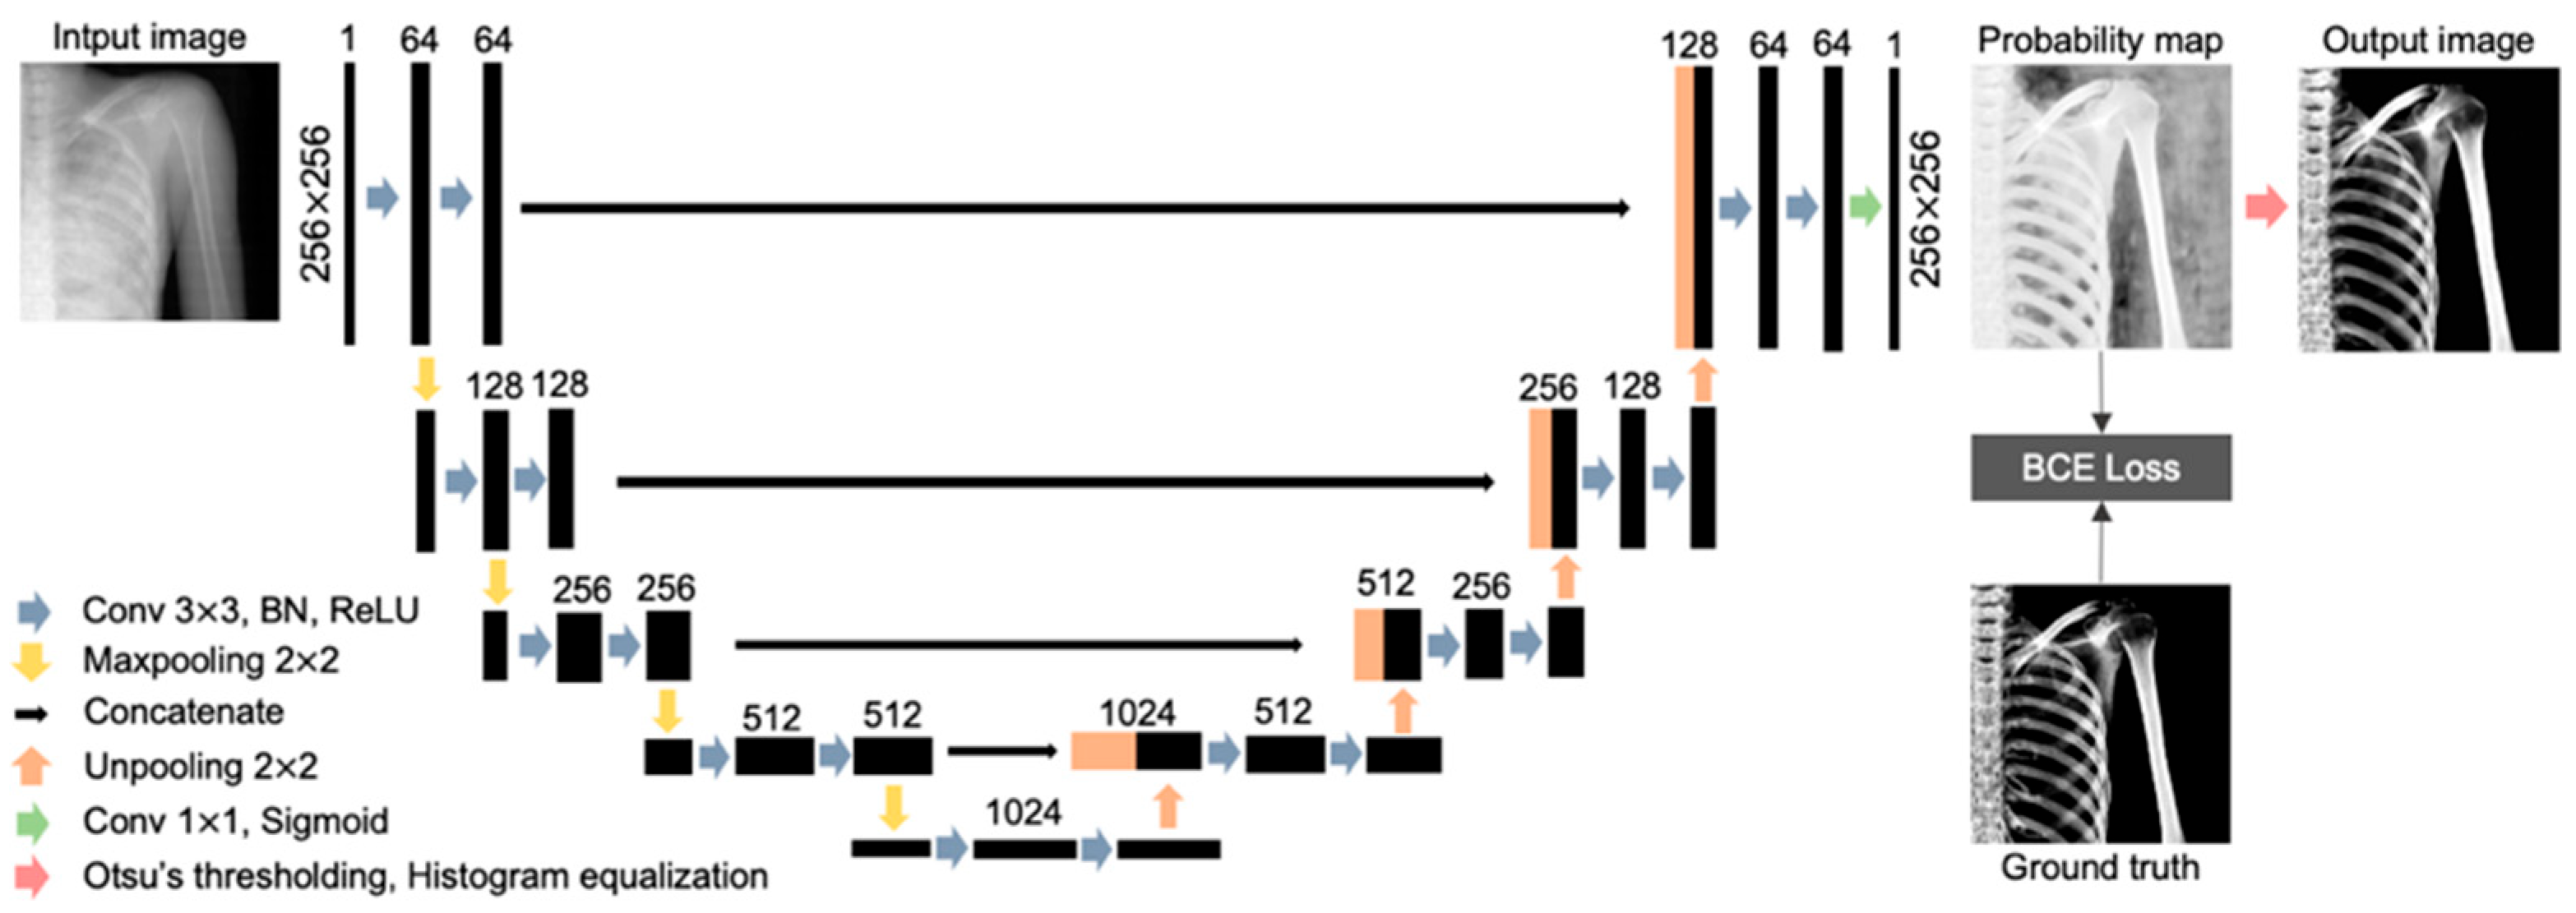

2.4. U-Net Architecture

2.5. Evaluation of Bone Extraction Performance by U-Net

2.5.1. Evaluation on the Extracted Bone Regions

2.5.2. Evaluation of Bone Signal Intensity Distribution